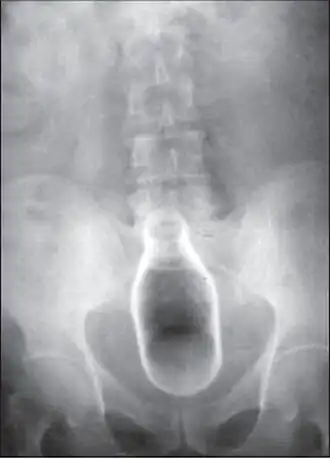

Обычно делают несколько рентгеновских снимков, чтобы точно определить место нахождения инородного тела. Инородные тела из малоконтрастного материала (например, пластика) могут потребовать ультразвукового исследования или компьютерной томографии.[28] Магнитно-резонансная томография противопоказана, особенно если неизвестен материал инородного тела. Инородные тела прямой кишки могут проникать глубоко в толстую кишку, при определённых обстоятельствах вплоть до правого изгиба ободочной кишки.[9]

Пища на растительной основе, особенно семена, такие как попкорн,[19] арбузные, подсолнечные и тыквенные семечки, могут слипаться в нижней части кишечника и образовывать безоары. Они приобретают клиническое значение, когда становятся слишком большими для нормального прохождения через анус. Этот вид ректального инородного тела встречается главным образом у детей, особенно в Северной Африке и на Ближнем Востоке, где эти семена составляют часть рациона.[20][21] В очень редких случаях семена в безоаре прорастают, будучи в нижнем кишечнике или прямой кишке, и вызывают блокаду.[22]